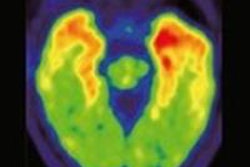

The new facility will be approximately 57,000 sq ft and will produce molybdenum-99, which decays into the diagnostic imaging agent technetium-99m. Technetium-99m is used in more than 40 million medical imaging procedures each year, primarily in stress tests to diagnose heart disease and in bone scans to stage cancer, Shine said.